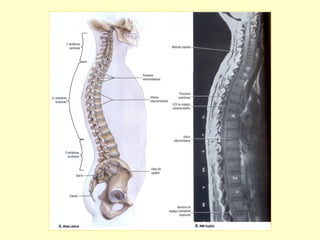

CURVATURAS

VERTEBRAIS

ANATÔMICAS